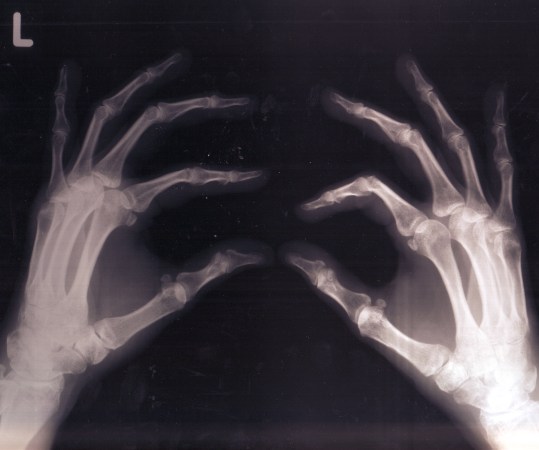

Bones, shown here in an X-ray, appear white because of the calcium they contain.